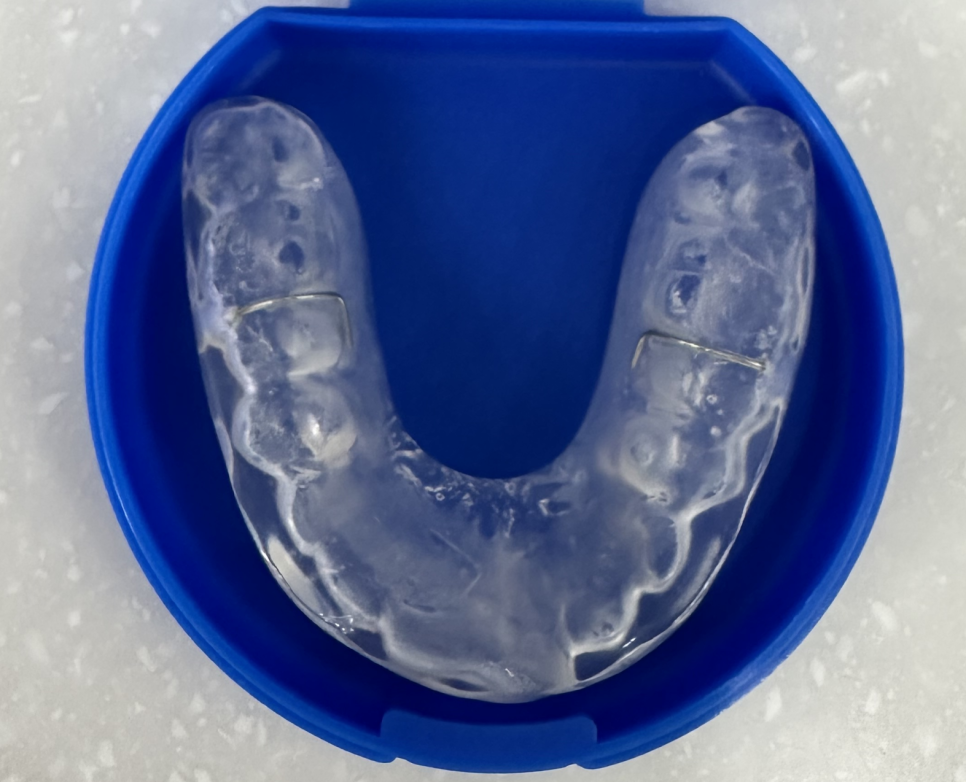

증상이 심할경우 장치 치료가 필요해요!!

필요한 경우 스플린트 장치나 물리치료 등 맞춤형 치료를 제안해 드립니다.

보톡스

장치 치료